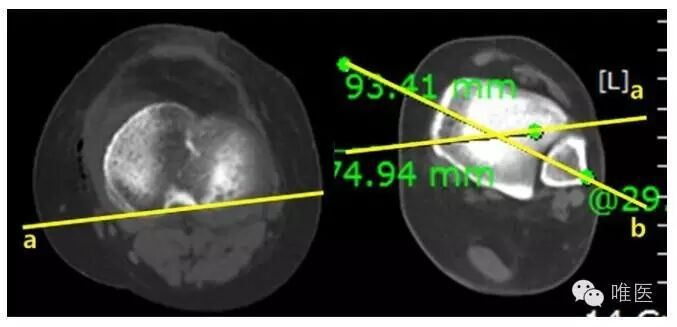

图示胫骨结节截骨角(TOA)的测量。通过CT测量近端胫骨后侧轴线和胫骨结节截骨轴线之间的夹角。TOA表明在横轴面上胫骨结节的后面冠状面截骨的方向。

术前、术后胫骨远端旋转角度(DTRs)平均值分别为27.80±6.20和24.20±8.00 (P=.006)。因此,OWHTO后胫骨远端内旋3.00±7.10。术前、术后HKA 角的平均值分别为:内翻7.60±2.70和外翻4.20±1.90(P<0.001),平均相差11.80±3.60。平均的截骨宽度(OW)12.8±3.2mm。胫骨平台内翻角(MPTAs)从术前的85.60±2.10增加到术后的95.70±2.50(P<0.001),平均相差10.10±3.50。胫骨平台后倾角(PTS)从术前的10.70±3.10增加到术后的11.30±3.00,平均相差0.70±2.20。胫骨结节截骨角(TOA)平均为19.10±3.30。